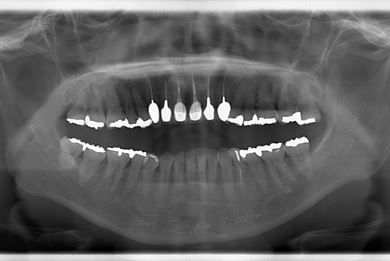

治療前

• 治療前